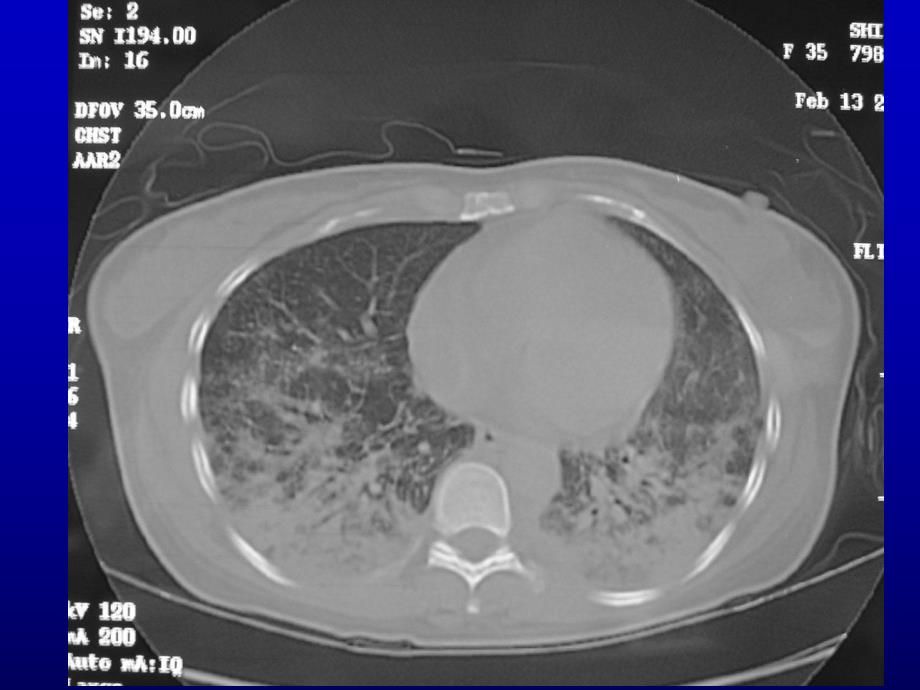

9、有杵状指。X线表现与病程有关,早期以毛玻璃样线表现与病程有关,早期以毛玻璃样改变、颗粒状、结节状影为主,进而可改变、颗粒状、结节状影为主,进而可出现网状、线状阴影,晚期表现为环状出现网状、线状阴影,晚期表现为环状或蜂窝状阴影以及肺容积缩小。另外,或蜂窝状阴影以及肺容积缩小。另外,可有肺门增大,肺门阴影模糊、肺不张,可有肺门增大,肺门阴影模糊、肺不张,胸膜增厚和胸腔积液。胸膜增厚和胸腔积液。类风湿性关节炎系统性红斑狼疮多发性肌炎和皮肌炎白塞病干燥综合征混合性结缔组织病类风湿性关节炎系统性红斑狼疮多发性肌炎和皮肌炎白塞病干燥综合征混合性结缔组织病肺功能表现为限制性的通气障肺功能表现为限制性的通气障

10、碍和弥散功能障碍,通常肺功能改碍和弥散功能障碍,通常肺功能改变先于胸部变先于胸部X线改变。线改变。类风湿性关节炎系统性红斑狼疮多发性肌炎和皮肌炎白塞病干燥综合征混合性结缔组织病某些多发性肌炎患者血清中存在某些多发性肌炎患者血清中存在抗抗J0-1抗体,这些抗体阳性的患者,抗体,这些抗体阳性的患者,与与PM-DM有关的间质性肺疾病(有关的间质性肺疾病(ILD)的发生率相当高,约占的发生率相当高,约占50%。类风湿性关节炎系统性红斑狼疮多发性肌炎和皮肌炎白塞病干燥综合征混合性结缔组织病诊断要点诊断要点l干咳、喘息性咳嗽、杵状指、干咳、喘息性咳嗽、杵状指、Velcro啰音;啰音;l胸片提示间质肺炎、肺